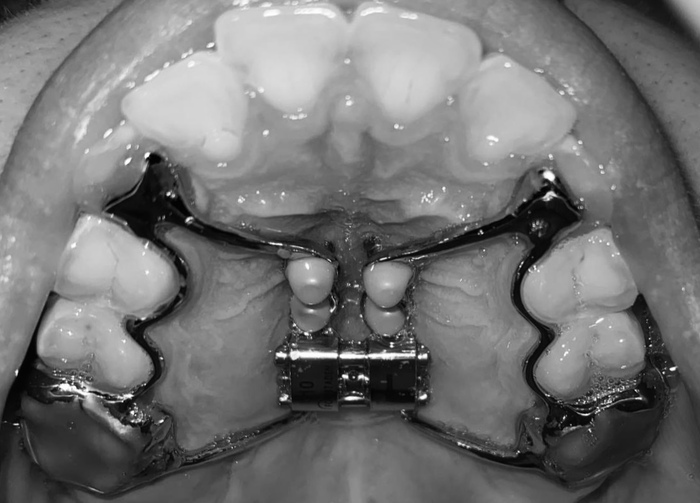

Мне удалили молочные клыки и изготовили ортодонтическую пластинку, ее еще называли «скоба», которую я исправно носила, но она почему-то мне нисколько не помогла…

И в один прекрасный день мы с родителями поехали в НН в Детскую областную больницу для дальнейшего ортодонтического лечения.

Там мне почему-то не сделали даже просто рентген, не говоря уже о КТ и забили болт на отсутствие семерок в зубном ряду, поставили «сапфировые» брекеты (которые постоянно окрашивались в желтый цвет)